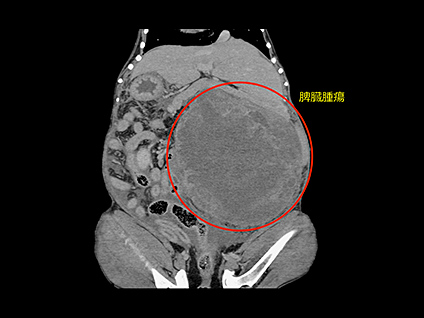

腫瘍性疾患におけるCT検査

腫瘍性疾患のCT検査は、病変の位置や浸潤、転移の有無など、手術前の検査としての役割や、抗癌剤などの治療効果判定としての役割があります。病変部やその周囲を細かく立体的にイメージできるようになるため、「より安全な手術、癌の早期発見」につなげる事ができます。